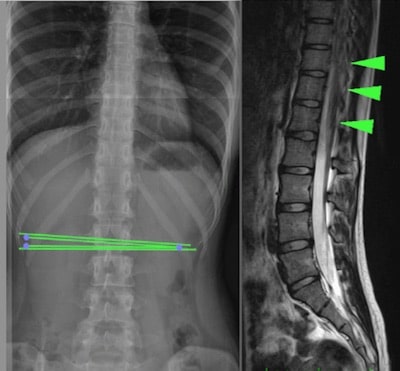

Фиксированный спинной мозг со скрытой спина бифида или “Occult Tethered Cord Syndrome” происходит из-за мальформации, которая образуется при неполном развитии спинного мозга (обычно в поясничном отделе) путем фиксации спинного мозга и провоцирует механическое натяжение и повреждения спинного мозга и позвоночного канала. (Рис.1).

Для диагностики необходимы такие исследования, как магнитно-резонансная томография (МРТ), компьютерная томография (КТ) или рентген позвоночника в зоне фиксации.